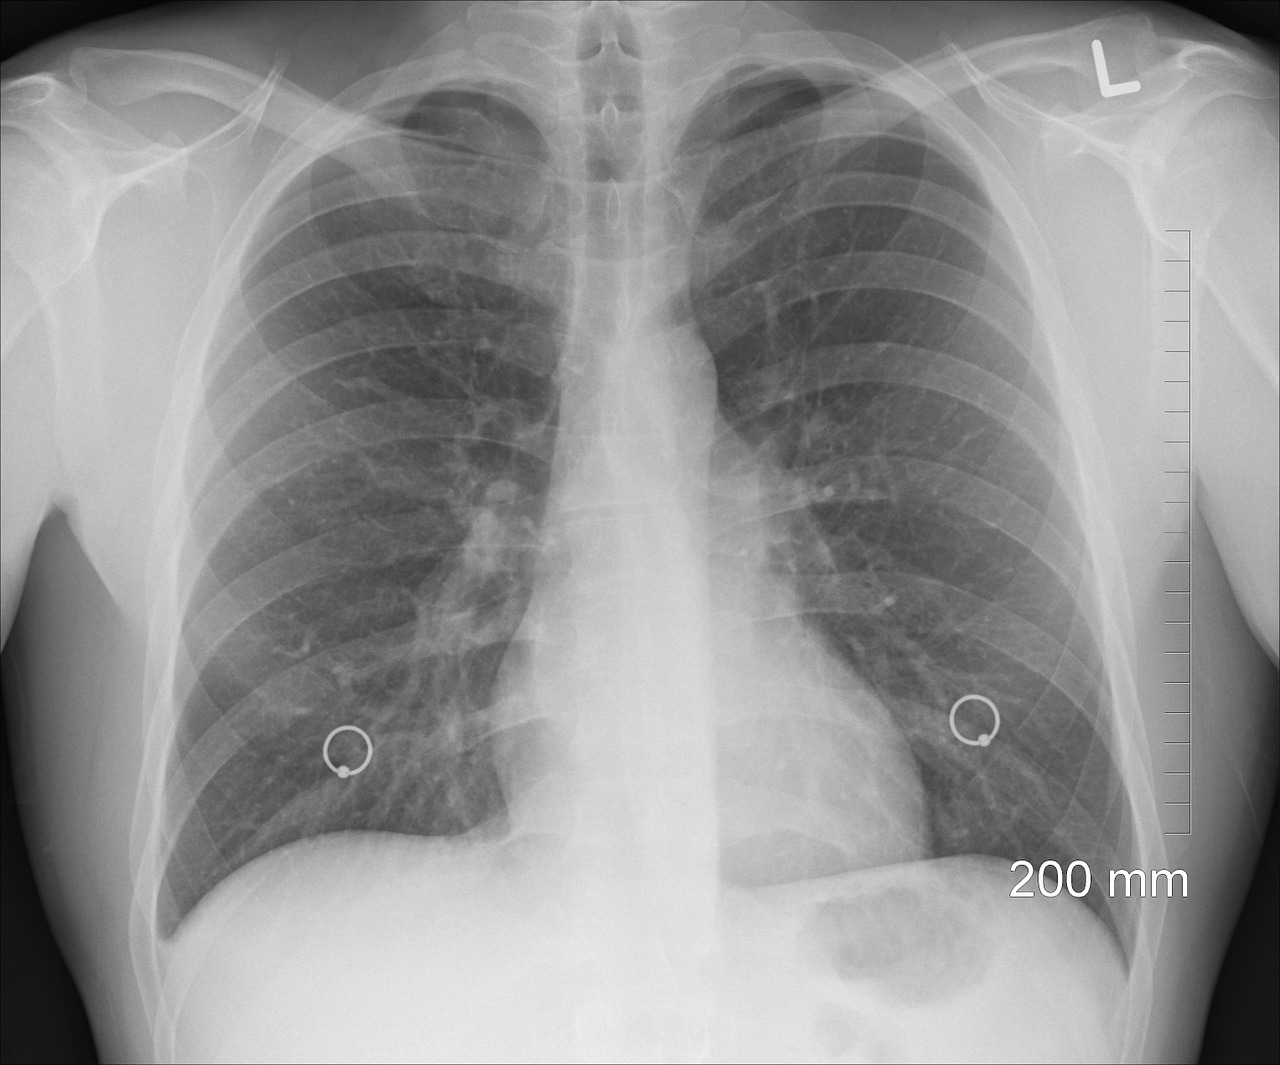

Pierwsza ważna zmiana w zaleceniach dotyczy stawiania diagnozy. – W ostatnich latach diagnostyka poprawiła się, radiolodzy wykonujący badanie tomograficzne wcześniej zauważają zmiany w płucach, pacjenci trafiają do nas na wcześniejszym etapie choroby – mówi dr Katarzyna Lewandowska, która od wielu lat zajmuje się pacjentami z IPF w I Klinice Chorób Płuc Instytutu Gruźlicy i Chorób Płuc. Po to, by usprawnić proces diagnozy, eksperci postulują, by nie było konieczne wykonanie biopsji. – Większość pacjentów to osoby starsze, mające choroby współistniejące. Biopsja może u nich spowodować zaostrzenie choroby. Powinna być wykonywana tylko wtedy, gdy pojawiają się wątpliwości dotyczące rozpoznania – wyjaśnia prof. Piotrowski.